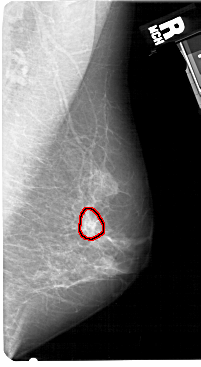

FILE: A_1520_1.RIGHT_CC.OVERLAY

TOTAL_ABNORMALITIES 1

ABNORMALITY 1

LESION_TYPE CALCIFICATION TYPE PLEOMORPHIC DISTRIBUTION CLUSTERED

LESION_TYPE MASS SHAPE IRREGULAR MARGINS SPICULATED

ASSESSMENT 4

SUBTLETY 3

PATHOLOGY MALIGNANT

TOTAL_OUTLINES 1

BOUNDARY